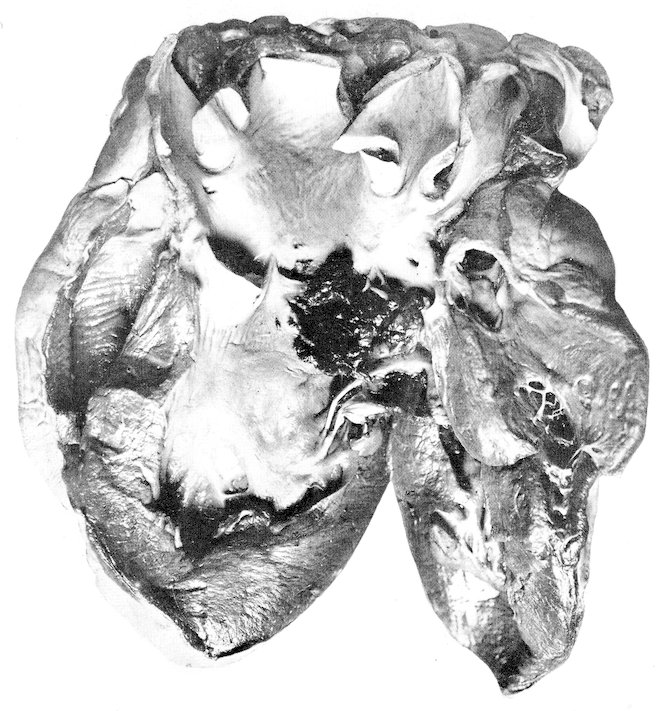

Some attention has been given to the study of diets for the wild specimens of our Garden, but no systematic observations have been made or records kept upon purely physiological subjects. Reference will be made at appropriate places to accepted comparative physiological facts, but our statistics permit additions to such knowledge only in a limited manner and in isolated instances. Doctor Corson-White has very ably summarized the diet, alimentary tract and physiology of the zoological groups with the pathology as found in our records.

A word might be added here as to the destruction of animals by injury from fighting and harassment by others in the cage. Fighting doubtless causes death, especially when males are together, but it is our experience that in cases of traumatic death search should always be made to see if the resistance of the dead animal had not been reduced by some disease. This is well illustrated in birds. Very frequently a specimen will come to autopsy with its head feathers plucked out, or with a billthrust in the wing or pelvic region. Such birds are not infrequently suffering from malaria, or heavy intestinal parasitism or from organic disease whereby the resistance and self-preservatory power has been decreased.

The foregoing survey of the approach to our subject reveals the multiplicity of factors which affect the study of comparative pathology. No one of them can be entirely omitted, no one is without some effect upon the origin and expression of disease, and no one is fully understood. Yet it is to be hoped that a study of our material, accumulated under routine conditions and uninfluenced by any experimental procedures, will demonstrate the natural response of various zoological groups to morbific agencies. Perhaps reactively some of the modifying 41conditions may thus be understood. It is also not unreasonable to expect that alterations observed as natural responses in a large number of specimens in nearly normal surroundings would serve as more reliable guides to investigative speculation than would changes in a few animals under artificial technical experimentation. We hope that the few facts we have been able to record may afford someone a basis for further biological studies. It is also to be hoped that something has been learned which in the end will afford an explanation of the diseases of man. Too great optimism in this direction should be guarded against because the human being is indeed an animal sui generis and, from the standpoint of normal conditions of nature, a wild animal.

The zoological classification found on pages 43–46 was compiled in 1903 by Dr. A. E. Brown on the basis of the British System. With a few exceptions the computations in the text are made on the basis of zoological orders since the number of specimens in families is often too small and the complications of so many different figures would be confusing. The tables will be found to correspond to the sequence of the classification. Dr. Corson-White has, however, used for her analysis the dietary groupings. A carnivore in her chapter implies strictly a meat-eater, in the rest of the book one of the zoological group Carnivora.